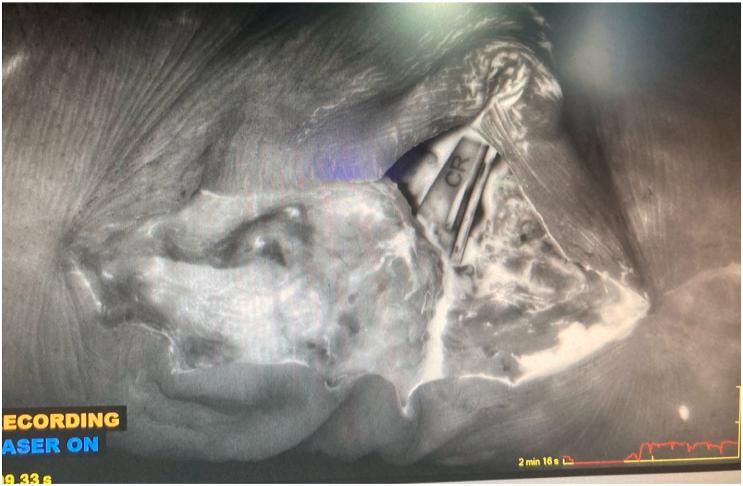

激光辅助吲哚菁绿血管造影术作为复杂关节置换软组织管理决策的临床辅助手段

Laser-Assisted Indocyanine Green Angiography as a Clinical Adjunct for Complex Arthroplasty Soft Tissue Management Decisions.

Soft tissue management is critical to successful perioperative management of total joint arthroplasty patients. Patient medical and surgical history can significantly complicate the soft tissue envelope of a patient undergoing primary or revision arthroplasty. Here we present 2 cases demonstrating the use of Laser-Assisted Indocyanine Green Angiography in evaluating tissue perfusion perioperatively. The information obtained with Laser-Assisted Indocyanine Green Angiography serves as a valuable clinical adjunct for surgeon decision making for total joint arthroplasty soft tissue coverage. This report demonstrates the clinical value of this underutilized tool, in an effort to highlight its effectiveness and potential uses for arthroplasty surgeons.

摘要

软组织管理对于全关节置换患者的围手术期成功管理至关重要。患者的内科和外科病史会显著增加初次或翻修关节置换患者软组织包膜的复杂性。在此,我们展示2例病例,说明激光辅助吲哚菁绿血管造影术在围手术期评估组织灌注中的应用。通过激光辅助吲哚菁绿血管造影术获得的信息可作为外科医生在全关节置换软组织覆盖决策中的宝贵临床辅助手段。本报告展示了这一未得到充分利用的工具的临床价值,旨在突出其对外科关节置换医生的有效性和潜在用途。